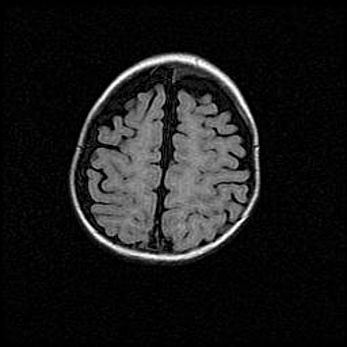

Неполная лизэнцефалия (пахигирия). Открытая гидроцефалия.

Возраст: 17 дней

Вес: 3110 г

Пол: мужской

Окружность головы: 33,5 см

Срок гестации: 35-36 недель

Лизэнцефалия—недоразвитие корковой пластинки и мозговых извилин в результате нарушения миграции нейронов коры. Поверхность мозговых полушарий гладкая. Микроскопически выявляется отсутствие нормальных слоев коры и скопление групп нейронов в подкорковом белом веществе.

Пахигирия—уменьшение числа вторичных извилин. В пораженном полушарии нервные клетки образуют толстый недифференцированный слой с неправильно расположенными нервными волокнами и группами гетеротопных клеток. Нервные клетки незрелые. Белое вещество истончено. При этом нередко аномально развит корково-спинномозговой путь.